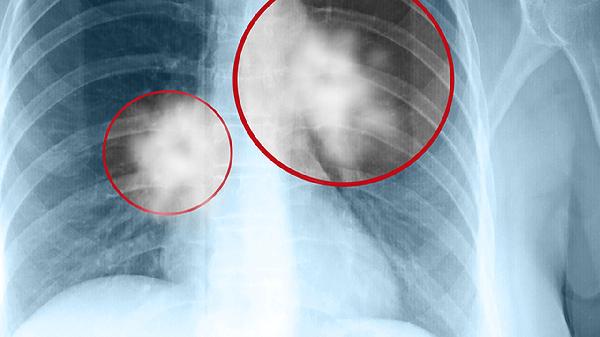

肺根是胸部外科手術(shù)的關(guān)鍵區(qū)域,肺葉切除、全肺切除等手術(shù)均需在此處分離和結(jié)扎相應的結(jié)構(gòu)。肺根淋巴結(jié)是肺癌轉(zhuǎn)移的常見部位,其狀態(tài)是肺癌分期的重要依據(jù)。肺根結(jié)構(gòu)的病變,如淋巴結(jié)結(jié)核、腫瘤壓迫等,可能引起支氣管狹窄、肺不張或上腔靜脈綜合征等一系列臨床癥狀。

了解肺根的解剖結(jié)構(gòu)對于理解肺部生理、診斷胸部疾病以及實施胸部手術(shù)都至關(guān)重要。保持肺部健康應注重避免吸煙、減少空氣污染暴露、預防呼吸道感染。定期進行低劑量螺旋CT等檢查有助于早期發(fā)現(xiàn)肺門及肺根區(qū)域的異常。若出現(xiàn)持續(xù)咳嗽、咳血、胸痛或呼吸困難等癥狀,可能與肺根區(qū)域結(jié)構(gòu)受累有關(guān),建議及時前往呼吸內(nèi)科或胸外科就診,通過胸部CT、支氣管鏡等檢查明確診斷。